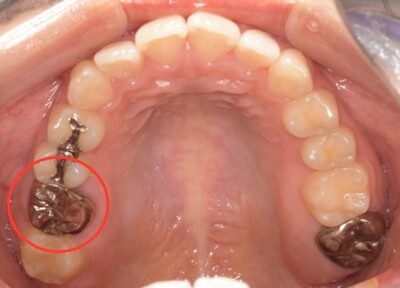

初診時口腔内写真

初診時パノラマX線写真と口腔内写真。

右上6に腫脹と排膿がみられた。

抜歯予定の歯と移植予定の歯

右上6抜歯後

右上6(青丸)を抜歯し、右下8(赤丸)を移植することを計画した。

右上の抜歯後の治癒を待つため、抜歯の1ヶ月後に移植を行うこととした。